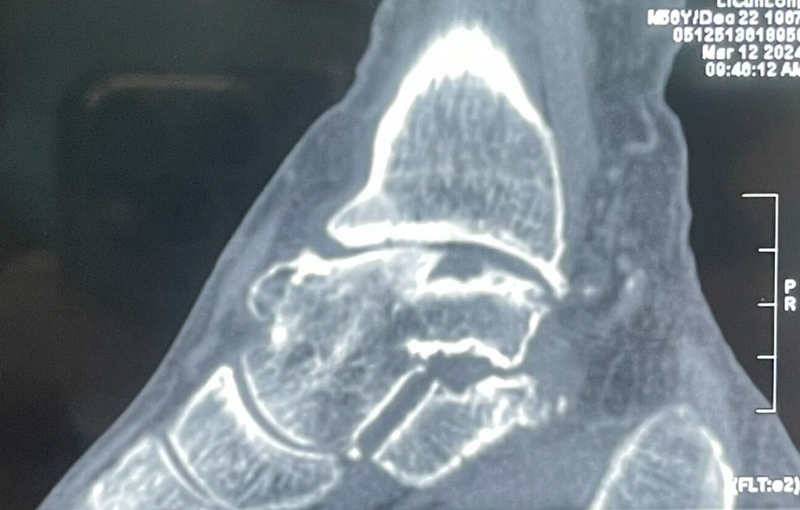

病例报告之二,xx,男,56岁,左踝创伤性关节炎。左踝崴伤6年,疼痛加剧3年。切口显露同前。

手术前资料